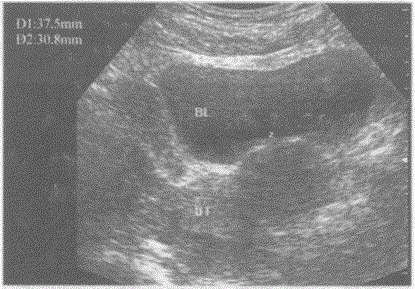

问题 临床资料:女,49岁,常规体检。 超声综合描述:子宫形态失常,宫体左侧可见3.7cm×3.1cm低回声,边界清晰,形态规则,内回声均匀,向外突起。 超声提示:

选项 A.左卵巢实性占位 B.子宫肌瘤(肌壁间) C.子宫肌瘤(浆膜下) D.阔韧带肌瘤

答案 C